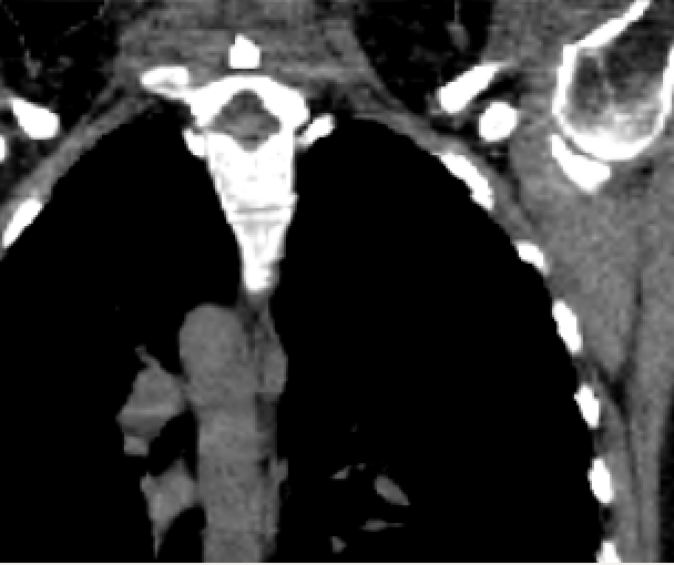

The mean DICE coefficients of the single-atlas registration of the liver and lung masks to the new static patient yield satisfying values of 0.860.12 and 0.960.09. Note the clearly different scan ranges of the data sets (Fig. 2a). The animation of the relevant structures is shown as an example in Fig. 3, using a variable real breathing signal of the target patient (Fig. 2b). In the puncture-relevant liver region, the patient’s breathing states are simulated plausibly for the 4D reference patient (Fig. 3) and, more importantly, the 3D patient (Figs. 4, 5), to which the motion model of was transferred333Demo movie, click here.

We achieve qualitatively plausible results for the liver area in this feasibility study. In the upper thorax especially at the rib cage in neighborhood to the dark lungs stronger artifacts can occur (Fig. 5c). They are due to problems in the inter-patient registration that is a necessary step for the transfer of the motion model. The non-linear deformation sometimes is prone to misaligned ribs. The same is true for the lower thorax with perforation first of the liver and then diaphragm (Fig. 4c). Further optimization have to be carried out as artifacts can appear on the high contrast lung edge (diaphragm, ribs) with a small tidal volume. For liver punctures only, the artifacts of smeared ribs are minor as can be seen in Fig. 4.